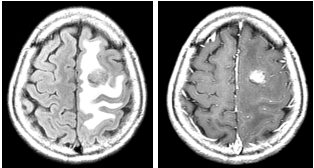

77 61 歲男性,右側半身無力。根據此二張 MRI 影像,左圖是 FLAIR,右圖是注射 Gd-DTPA 的 T1WI, 最適當的診斷是:

(A) Acute MCA infarction with cytotoxic edema (B) Acute ACA infarction with cytotoxic edema (C) Metastasis with peripheral brain tissue edema (D) Subacute hematoma with peripheral brain tissue edema